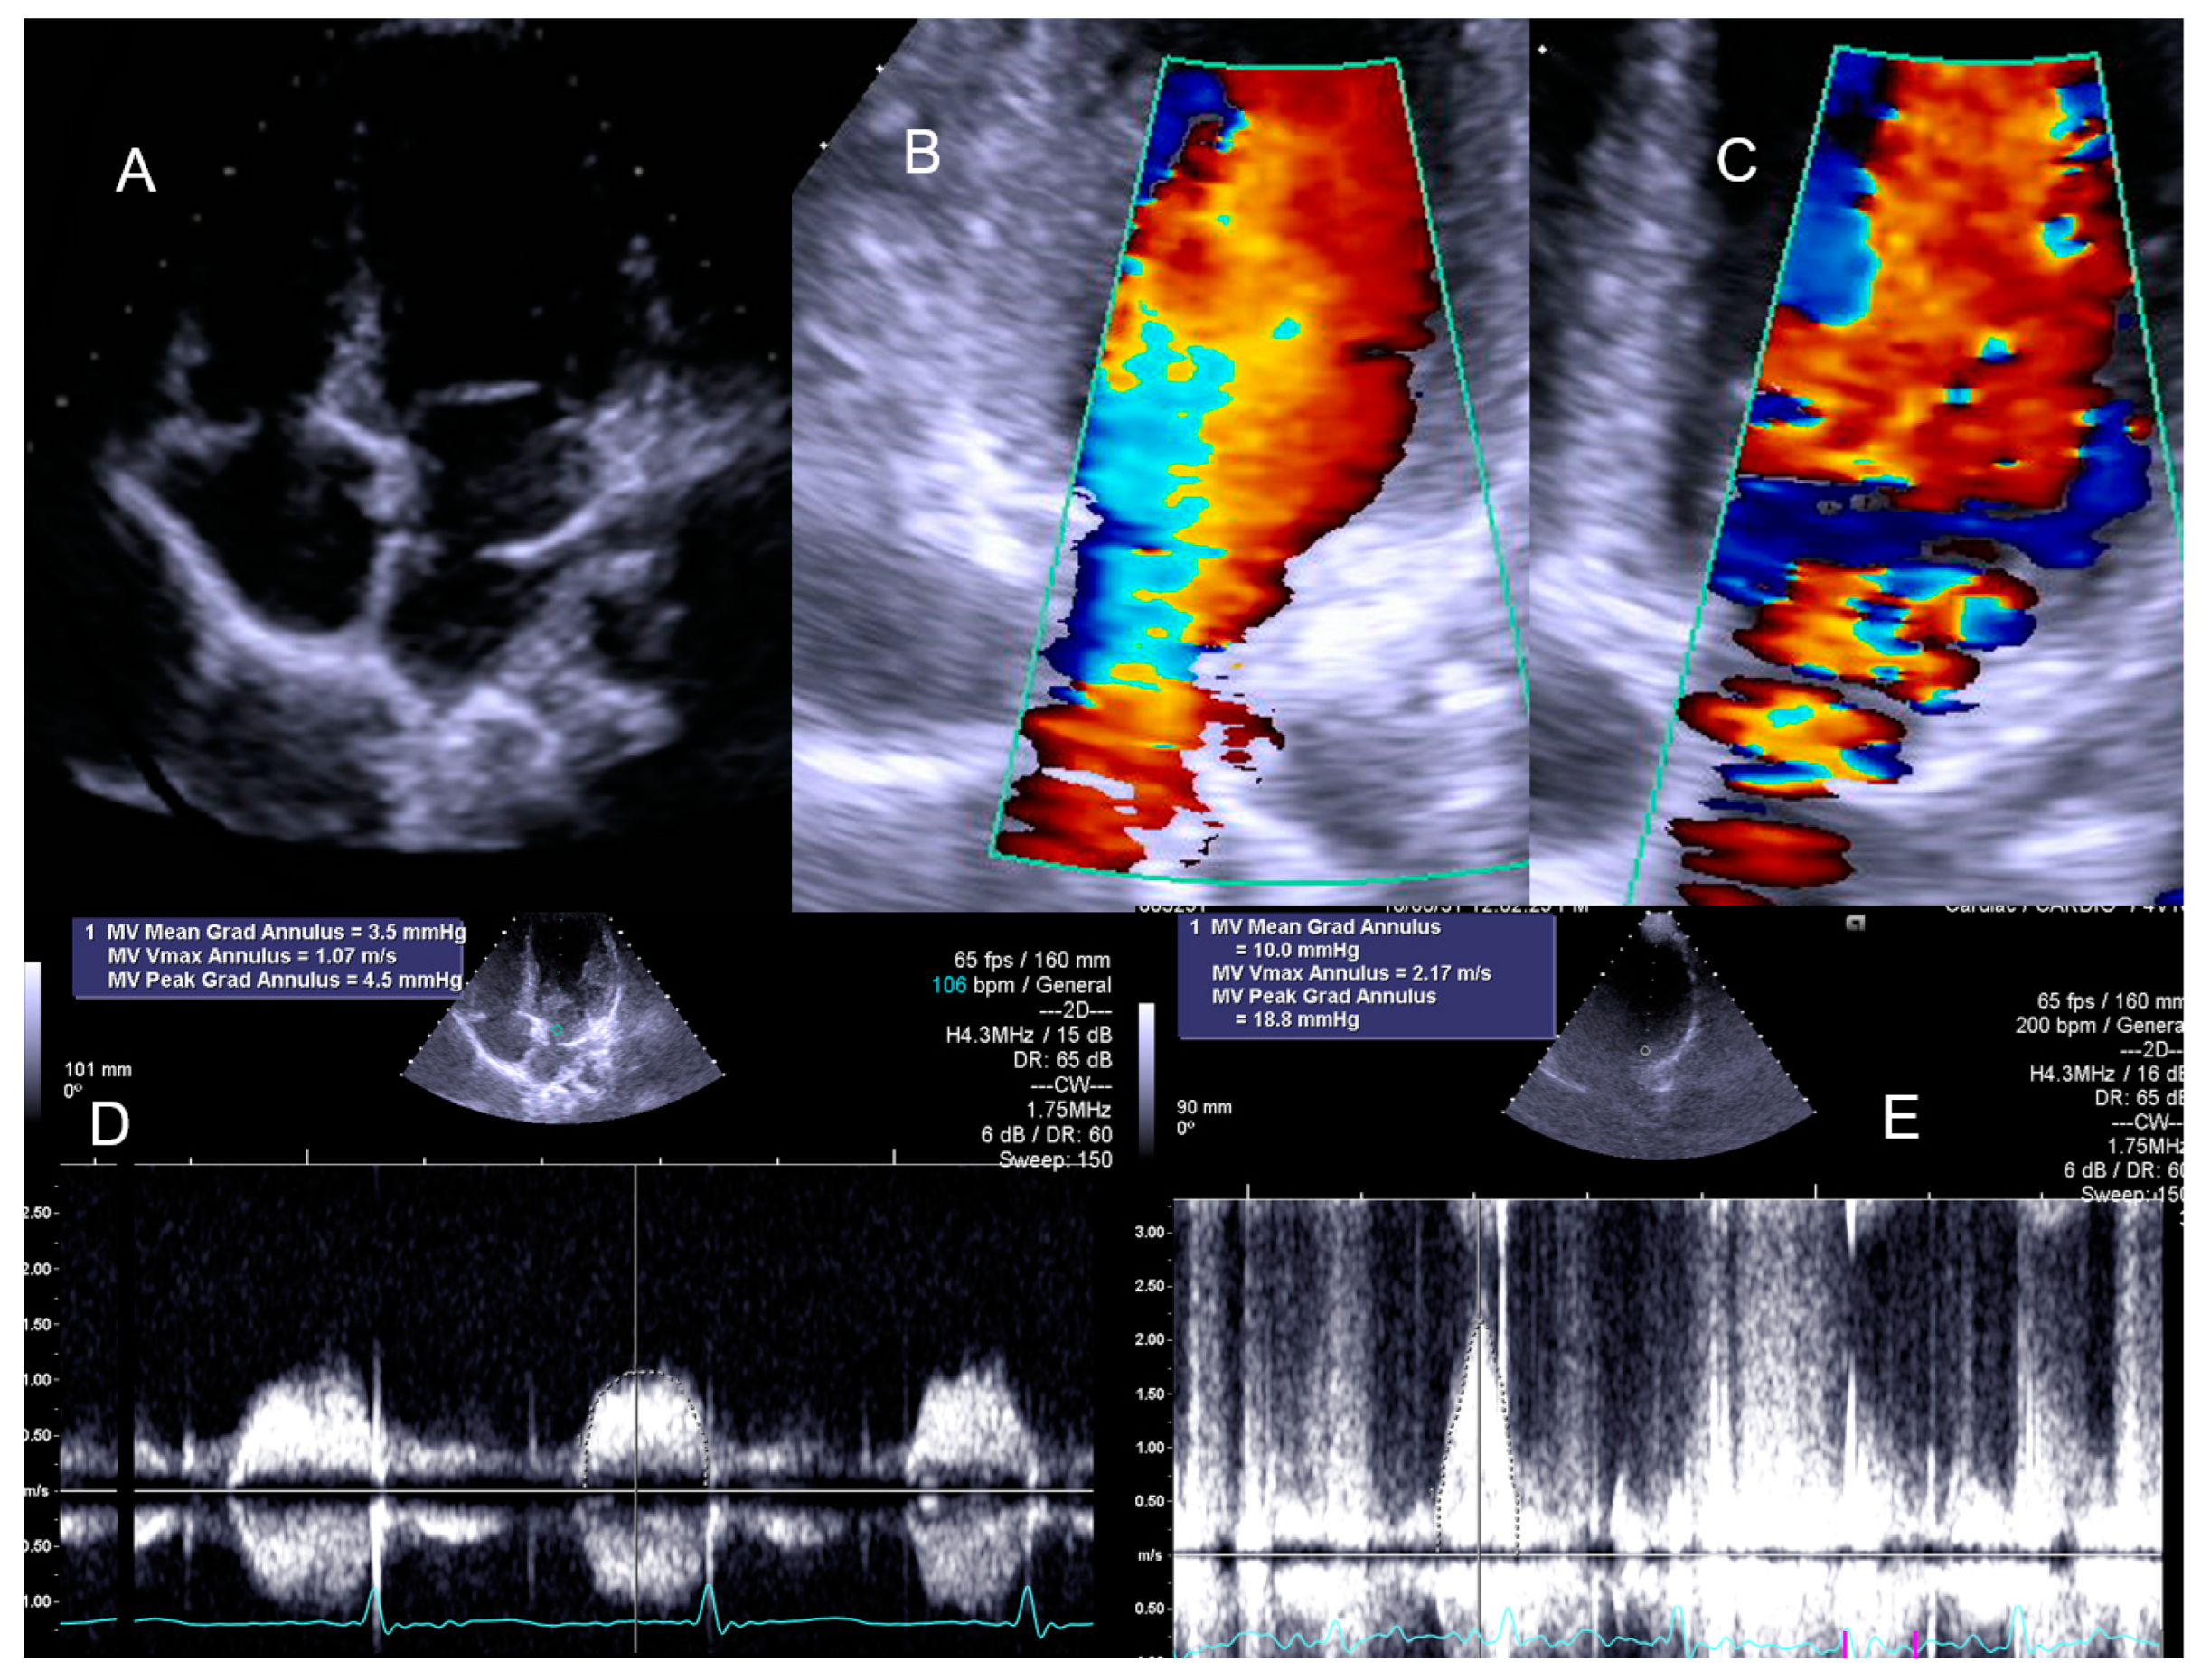

The child with Cortriatriatum sinister revealed a nonsignificant increase in the diastolic mean gradient (Figure 8).

Figure 8.

The exercise Doppler data in conjunction with the exercise and clinical data led the medical team to keep the patient in close clinical follow-up. (A): Intra–atrial septum in “cortriatriatum”; (B): color flow before exercise; (C): color flow at peak exercise; (D): continuous–wave (CW) flow before exercise; (E): CW flow at peak exercise [1].